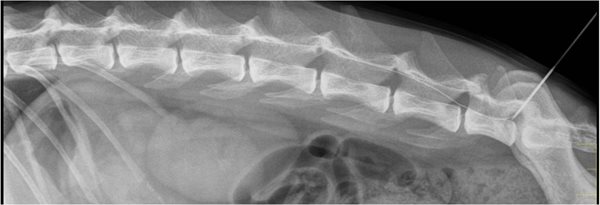

Chien

Labrador

2 ans

Pas d’antécédents médicaux

Accident de la voie publique il y a 1 h

Globe vésical

Motif de l’anesthésie: radiographies appendiculaire + pose d’un implant osseux

Tachypnée

Tachycardie

TRC=1 sec

Thorax :RAS

Vigilance ok

Abdomen: RAS

Fracture humérus D

Dermabrasions

Tachypnée, tachycardie, TRC = 1 sec: état de choc en phase compensée.

267 chiens AVP

38,9% ont présenté une lésion pulmonaire ou de la paroi thoracique

57,7% ont présenté plusieurs lésions thoraciques

36,3% des chiens ayant présenté une fracture avaient des lésions thoraciques

42,3% des chiens ayant présenté plusieurs fractures avaient des lésions thoraciques